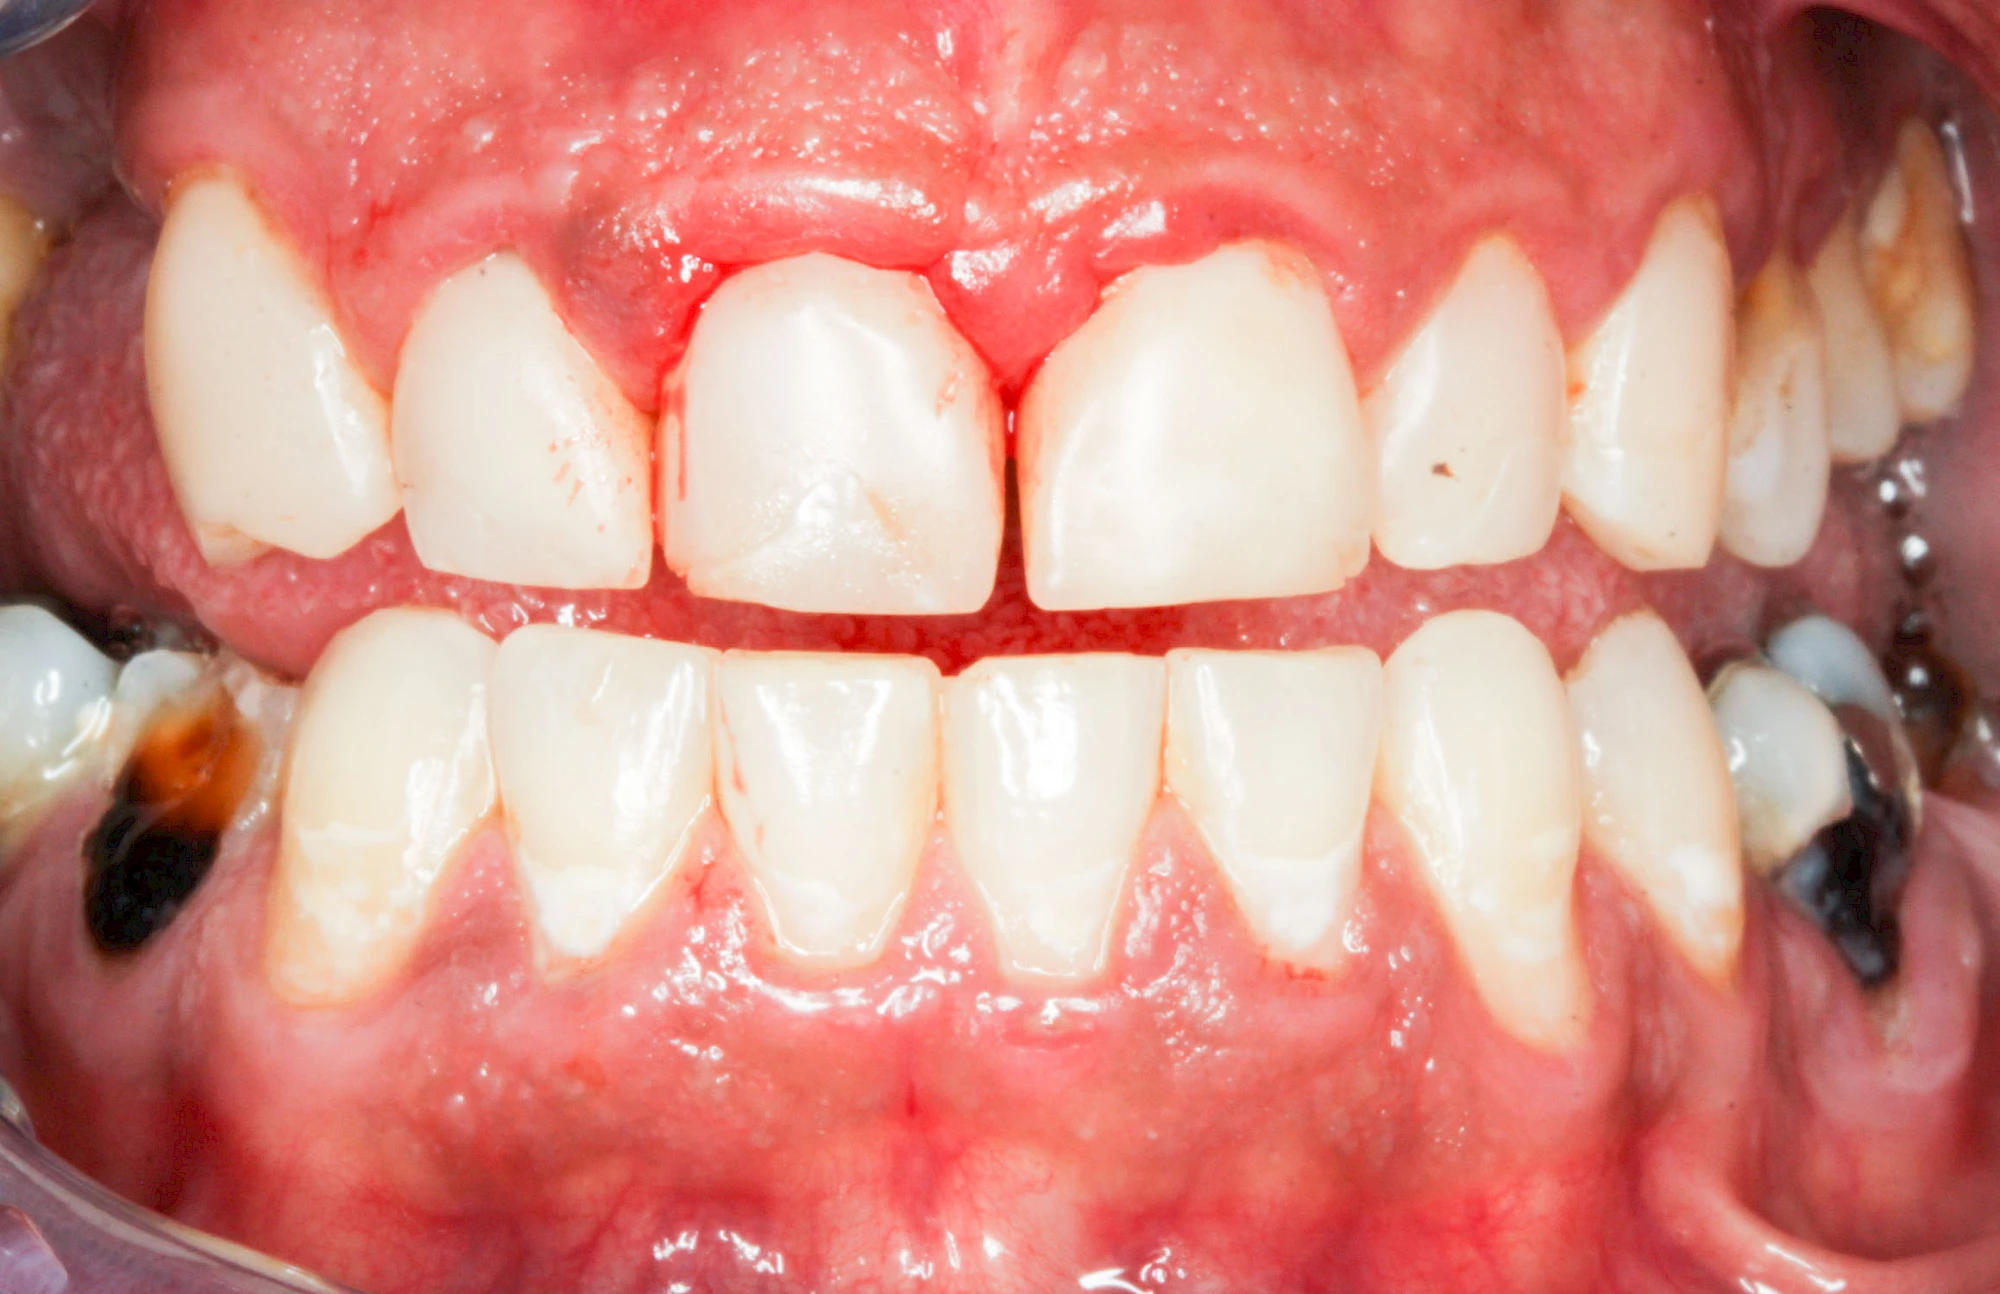

Bakterien in den Zahnbelägen greifen neben den Zähnen auch das Zahnfleisch (Gingiva) und den gesamten Zahnhalteapparat (Parodont) an. Der Körper reagiert mit einer Entzündung, sichtbar als Rötung und Schwellung. Meist blutet das Zahnfleisch z .B. beim Essen oder auch beim Putzen der Zähne.

Ist zunächst nur das Zahnfleisch von der Entzündung betroffen, spricht man von Gingivitis. Später, wenn auch der Knochen um die Zähne herum entzündet ist, spricht man von einer Parodontitis. Bei der Parodontitis wird der Knochen nach und nach abgebaut und das Zahnfleisch zieht sich zurück. Die Zahnhälse und Zahnwurzeloberflächen liegen mehr und mehr frei. Die Zähne werden zunehmend lockerer und fallen schließlich aus.

Bei Schwellung, Rötung oder Blutung des Zahnfleisches sollte neben der Intensivierung und Optimierung der Mundhyiene der Zahnarzt kontaktiert werden.